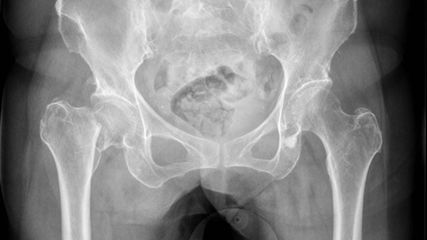

Abb. 2: Mediale und laterale Schenkelhalsfraktur